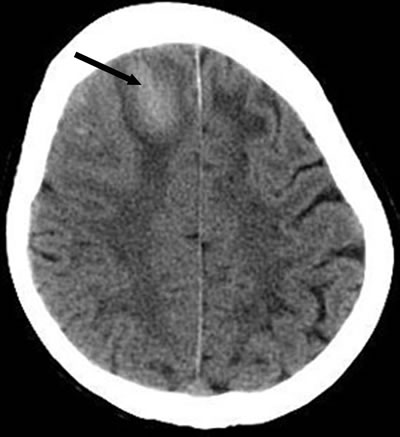

A 65-year-old woman presented with progressive walking instability, which first developed 7 months ago. This patient had no history of hypertension, diabetes, heart disease and tumor. She ignored the initial symptoms and did not go to hospital. Symptoms progressed and included headache, low-grade fever (temperature fluctuations from 100.4 °F to 102.2 °F), night sweats which persisted for 20 days with no nausea, vomiting, vertigo, malaise, visual changes, or weight loss. Physical examination showed that consciousness was clear, quarrel was not skewed, limb muscle strength and muscle tension was normal, Babinski’s reflex was negative, meningeal stimulation was positive and other physical observations were unremarkable. Laboratory tests showed that her white blood cell count, coagulation function, human immunodeficiency virus and tumor marker tests were normal. Smears and cultures for ordinary bacteria and fungi were negative. Analysis of the CSF revealed colorless and transparent fluid, pressure was more than 400 mm H2O, white blood cell (WBC) count 60×106/L, lymphocyte 97%, red blood cell (RBC) count 1240×106/L, protein level 5.6g/ L, glucose level 2.28mmol/ L, chloride 125mmol/ L, no tuberculosis and other bacteria were detected (Table 1). The patient’s brain CT image showed a high-density shadow of right frontal lobe, CT value was 65 Hu, and indicated ICH (Figure 1). Contrast MRI of her brain showed ICH in the right frontal lob, and LME (Figures 2, 3). Chest X-ray was normal. As the CSF showed elevation of inflammatory biomarkers, meningeal irritation was positive, and MRI supported a suspected CNS infection, CNS infection was proposed as the most likely diagnosis in this previously healthy adult. After CSF was sent for culture, we selected ceftriaxone to implement our choice of anti-infective therapy. Isoniazid, pyrazinamide and rifampin were used as an anti-tuberculosis treatment and mannitol was used to reduce intracranial pressure. An acid-fast bacillus in CSF was not found and the CSF culture was assessed as negative. Unfortunately, 2 days after admission, the patient suddenly lost consciousness and showed corectasis. The patient accepted emergency craniotomy and 4 days after admission, the patient died. Histopathologic examination confirmed the diagnosis of tuberculous meningitis (TBM).

Figure 1: Noncontrast brain computed tomography shows a hematoma (arrow) in the right frontal lobe.